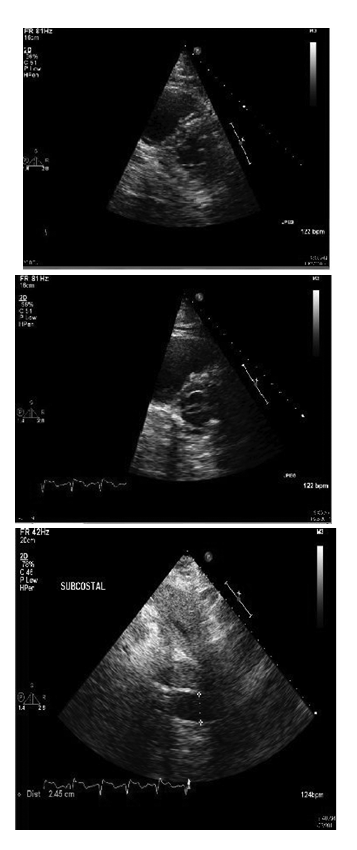

Subsequently, she had worsening dyspnea and hypoxia and was intubated. She remained hypotensive despite fluid boluses. Therefore, she was started on vasopressors. Initial laboratory findings included a normal leukocyte count and an elevated CRP of 67.4. Portable chest x-ray showed stable pulmonary vascular congestion but scattered pulmonary in filtrates. EKG showed sinus achy cardia with right fascicular block. There were mode stelevations of Troponin with a peak value of 4.7. Her initial arterial blood gas was interpreted as an acute uncompensated respiratory acidosis. An echocardiogram displayed findings of right ventricular dilatation with a pulmonary artery systolic pressure of 30­40mm Hg, D­shaped left ventricle and dilated inferior venacava, all suggestive of acute right ventricular pressure and volume over load (Figure 2). Anecho cardiogram performed 5monthsearlierrevealed normal right ventricular pressures without signs of failure. Cardiac catheterization was not performed as it was unlikely that myocardial ischemia was from anatomic obstructive coronary disease but rather was likely a result of global hypo perfusion.

Figure 2 Transthoracic echocardiogram showing images of dilated right ventricle with straightening of interventricular septum and the D­sign (top and center) and dilated inferiorvena cava (bottom).